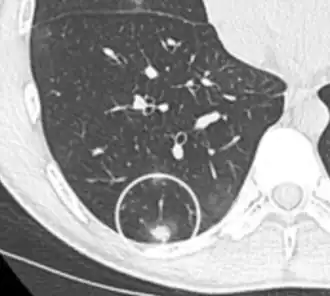

Low attenuating nodule (in this case a fat containing hamartoma).[9] -

Cavitation with relatively thick wall, in this case aspergilloma).[9]